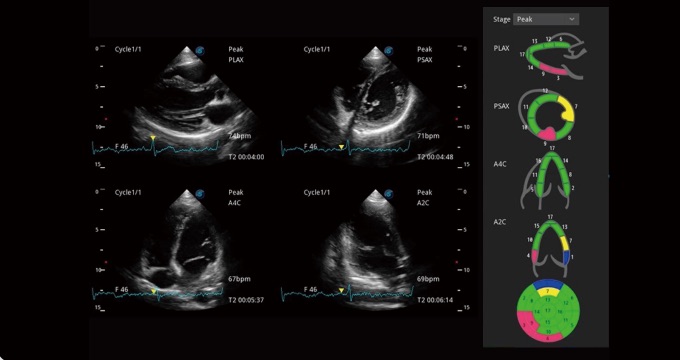

Single crystal transducers greatly improve signal ratio, acquire stunning images and provide superior sensitivity and resolution for both the near and far fields, by increasing the uniformity of crystal alignment and raising energy transmission efficiency. Single crystal C1-5 for abdominal and OB patients and S1-5 for cardiology and transcranial applications. Composite crystal linear transducers, by reforming the conventional piezoelectric materials, achieve a better acoustic spectrum and lower acoustic impedance to serve well in vascular, breast, thyroid, MSK, etc. The combo of 12L-A, 12L-B, 9L-A covers an ultra-wide frequency bandwidth, leaving nearly no blind spot for all sorts of scanning.